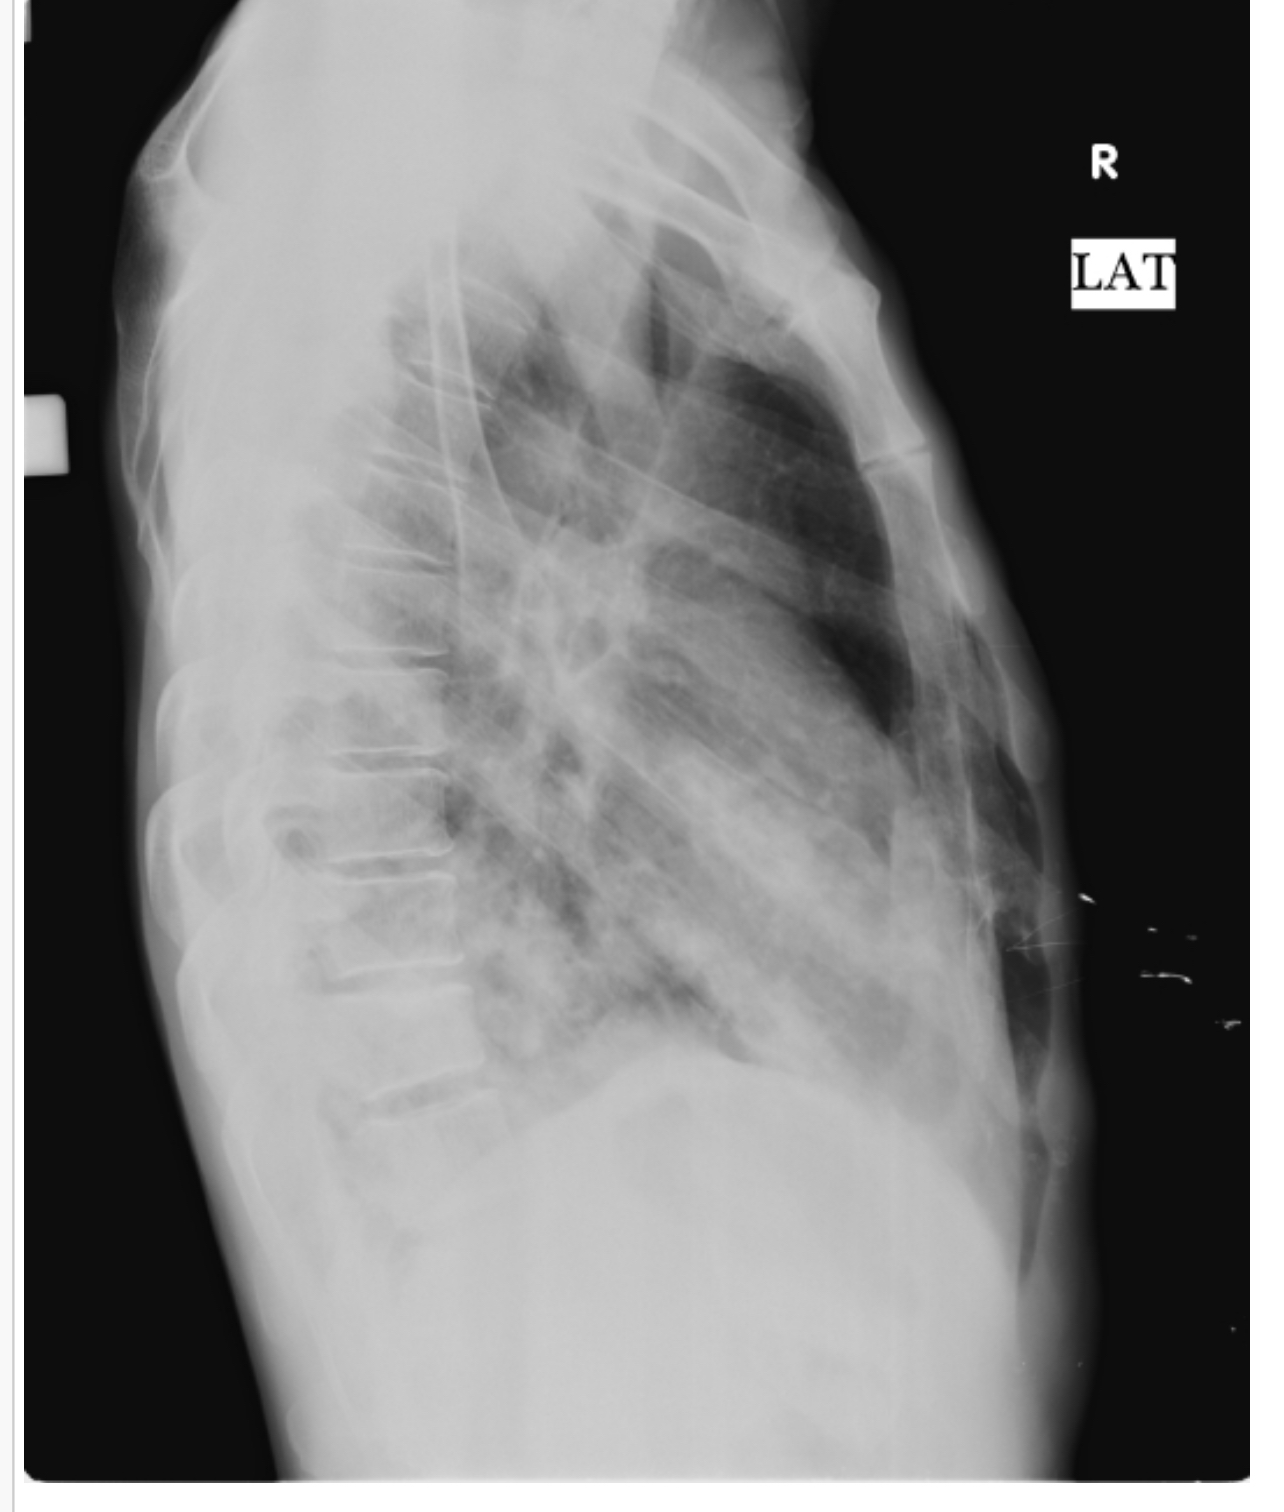

RESPIRATORY EXAMINATION

INSPECTION

Shape- Flattened

Trachea- appears to be central

Supraclavicular hollow- present

Infraclavicular flattening - present

Suprascapular wasting - present

Shoulder drooping - absent

Scoliosis/kyphosis/lordosis- absent

No engorged vein sinus or scars seen

PALPATION

All inspectatory findings have been confirmed

There is no rise of local temperature or tenderness

Trachea- central

Chest movements- Reduced on the right side

Vocal fremitus-reduced on the right side

Rib crowding - absent

Bong tenderness- absent

PERCUSSION

Right side dull note at mammary and inframammary areas

Left side resonant

AUSCULTATION

Right side - breath sounds reduced

Left side - normal

No rhonchi or wheeze heard

Findings: 1)E/O air bronchogarm in right lung

2) right lung consolidation

X-RayDIAGNOSIS

WITH RIGHT LOWER LOBE PNEUMONIA